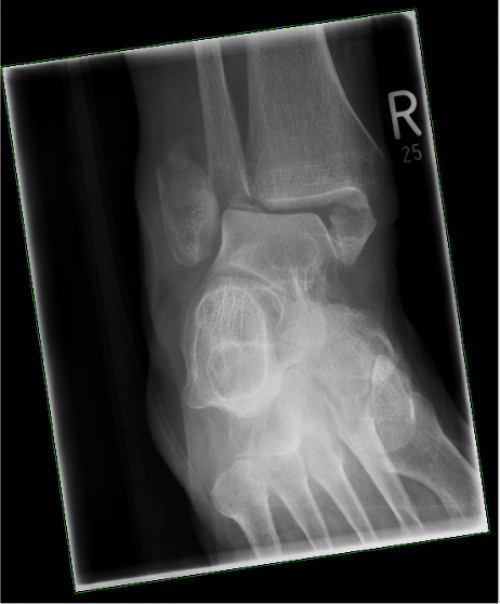

Nach dem ansonsten unauffälligen Bodycheck führen Sie eine Röntgenuntersuchung durch (siehe Abbildungen).